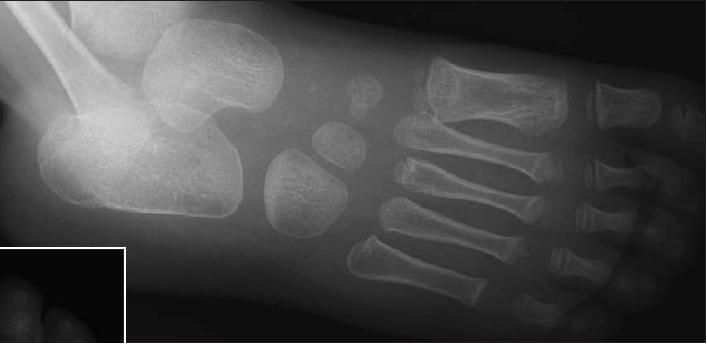

X-ray films of right foot as shown.

The x-ray films show sclerosis of the proximal cuboid bone (arrows), suggestive of cuboid compression fracture.